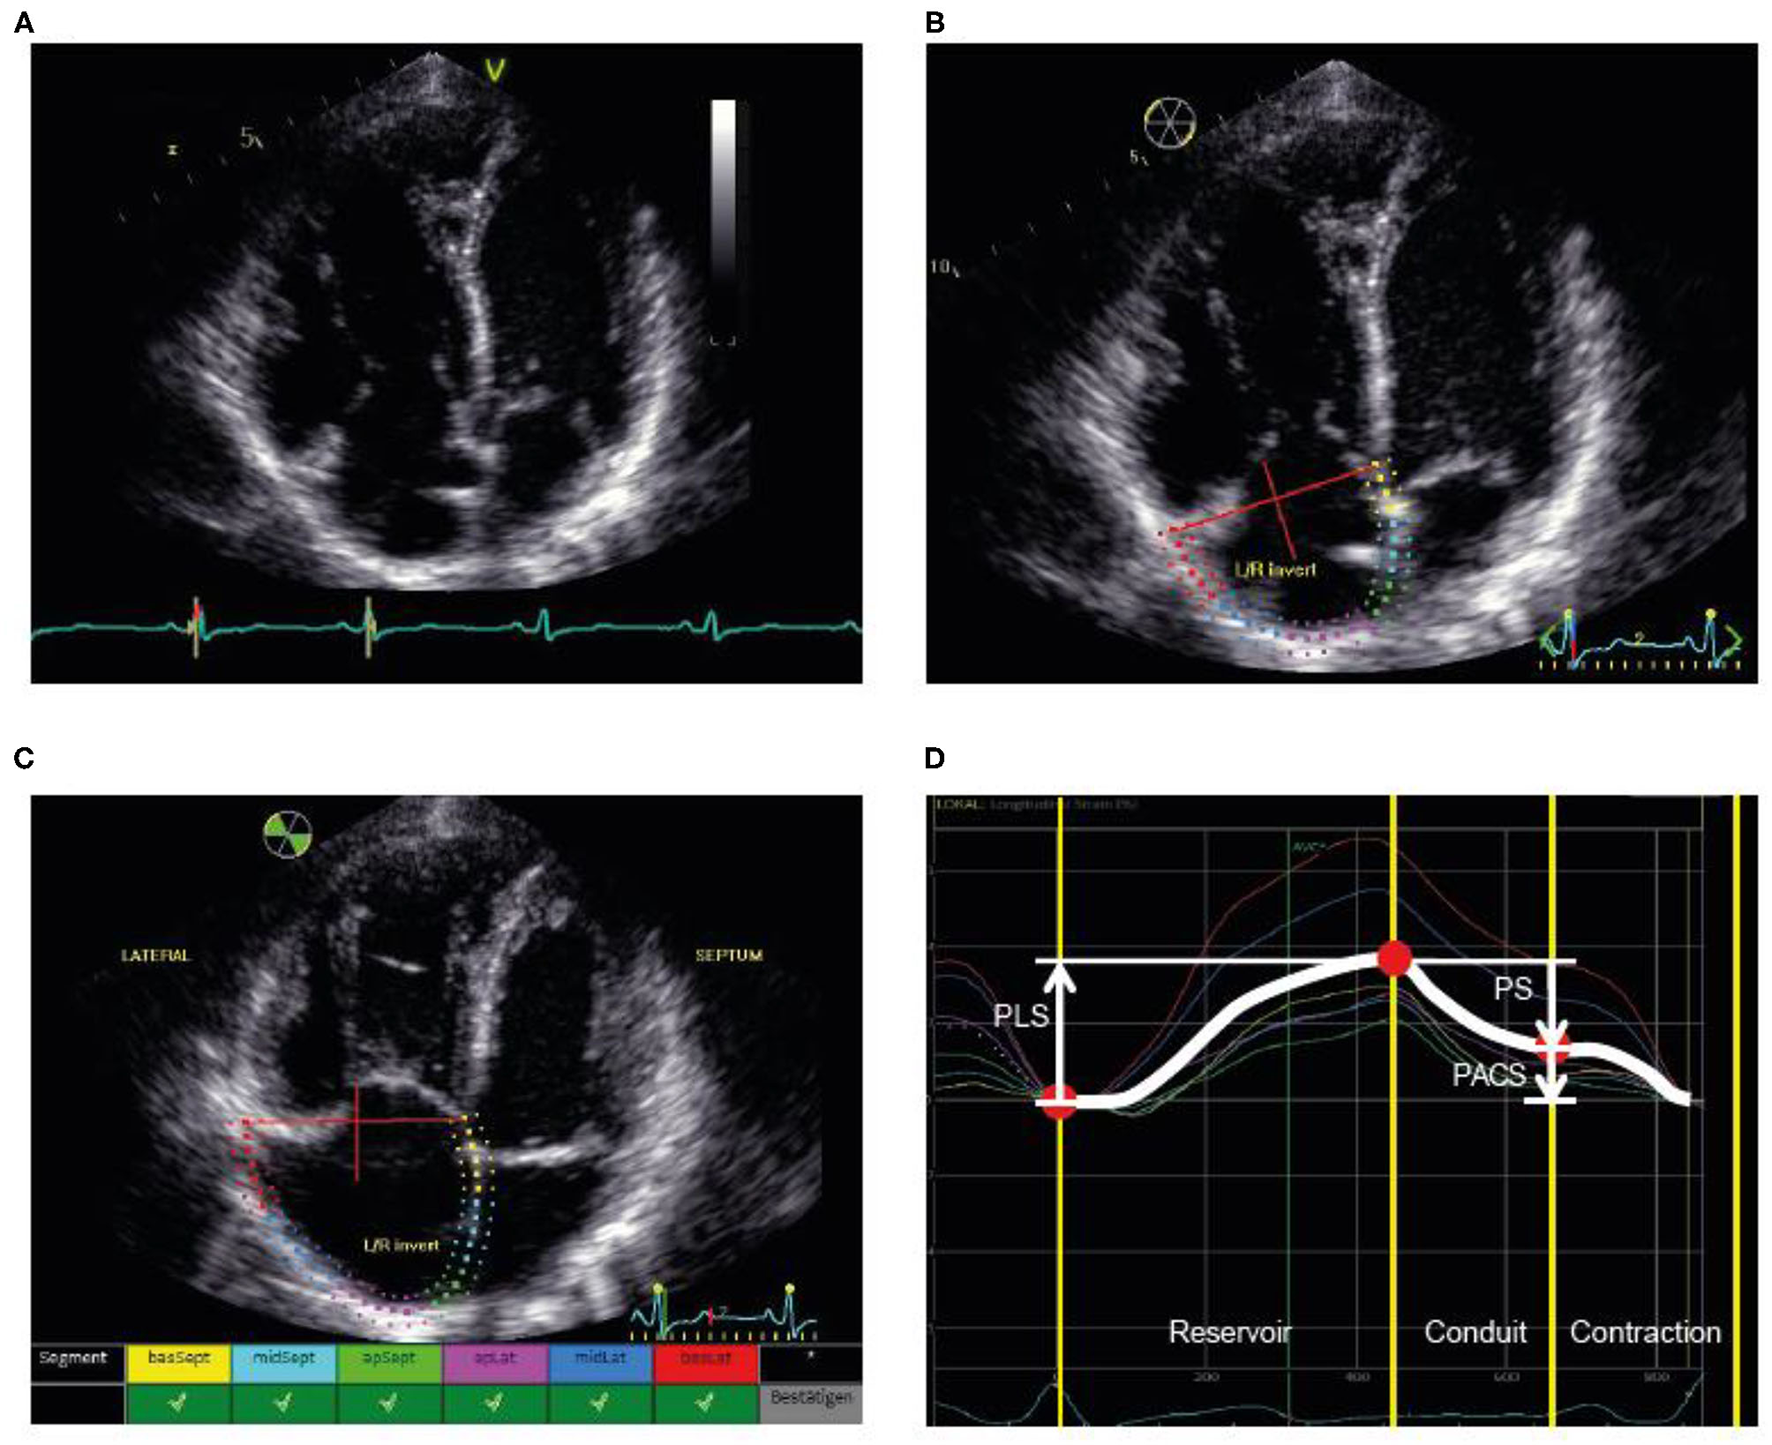

Tracing of the right atrium was performed as shown in Figure 1 according to the current recommendations (7, 19, 20). Using a right ventricle-focused apical four-chamber view, the region of interest was manually placed on the RA endocardial border. After automatic tracing of the six segments, every segment was manually adjusted to the thickness of the RA wall. The zero reference was set at the R wave and all the strains were positive. RA peak longitudinal strain (PLS) and peak active contraction strain (PACS) were assessed as measures of the reservoir phase and contraction phase, respectively. RA passive strain (PS), indicative of conduit function, was calculated from the difference between RA peak longitudinal and active strain as shown in Figure 1. Intra- and interobserver variability for PLS were assessed in a random subset (20%) of the cohort.

FIGURE 1

www.frontiersin.org

Figure 1. Illustration of the assessment of RA strain. (A) First, the RV-focused apical four-chamber view was used with selection of the cardiac cycle and adjustment of the electrocardiogram (to R-wave). (B) Second, the RA endocardial border was traced as the region of interest, covering the RA lateral wall, roof, and septal wall. (C) Third, processing provided an overview wherever speckle tracking was feasible for the selected regions. (D) Fourth, the different phases were identified and the strain values determined. PACS, peak active contraction strain; PLS, peak longitudinal strain; PS, passive strain; RA, right atrial; RV, right ventricular.